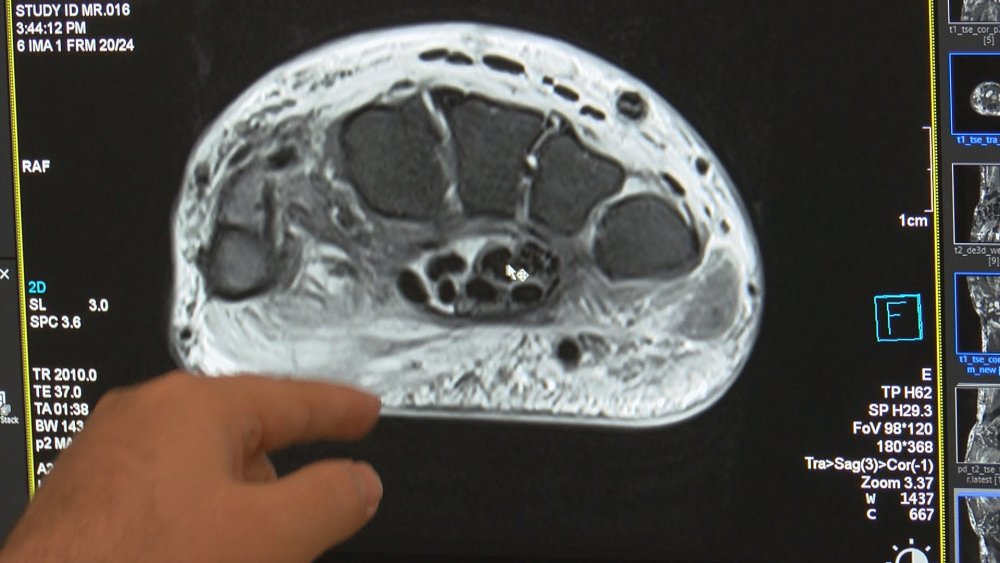

Nöroradyoloji Uzmanı Prof. Dr. Mustafa Özateş, cep telefonunun aşırı kullanımına bağlı olarak gelişen kas iskelet sistemi hasarlarına bağlı baş ve boyun ağrısı görülme yaşının, özellikle son 10 yıldır 15'li yaşlara kadar düştüğünü belirterek, "Son yıllarda el parmaklarının WhatsApp yazışmaları nedeniyle aşırı kullanımına bağlı gelişen ve tendonların mikropsuz iltihabı olarak tanımlayabileceğimiz "tendinit'le çok sık karşılaşıyoruz. Tıp camiasında kendi aramızda buna "whatsappit" demeye başladık, o kadar yaygın rastlıyoruz. Cep telefonunun aşırı kullanımı, kas ve kemik yapılarını bozuyor. Muhtemelen ileriki yıllarda kireçlenme vakalarını daha sık göreceğiz" dedi.

Telefonla konuşmanın iletişim açısından öneminin çok büyük olduğunu ama aşırıya kaçmanın sağlık tehditleri yarattığını kaydeden Prof. Dr. Özateş, "Boyundaki hem kas yapısı hem de kemik yapısını bozabiliyor, bunların fonksiyonlarını engelliyor. Muhtemelen ileriki yıllarda da ciddi bir kireçlenme artışı olacağını tahmin ediyoruz. Akıllı telefonlar postür bozuklukları, duruş anormallikleri ve buna bağlı olarak gelişen baş ve boyun ağrılarına yol açtığı gibi skolyoz dediğimiz omurganın eğriliklerine de neden olabiliyor. Son yıllarda gençlerde skolyoz çok görmeye başladık. 15-25 yaş arası gençlerde cep telefonlarının vücudunun doğal pozisyonunun dışında aşırı bir şekilde kullanılması neticesi o bölgelerde kemik yapılarının dizilimi bozuluyor, kas yapılardaki gerginlikler sonucu da sağlığı tehdit eder hale geliyor" diye konuştu.

"Örneğin bademcik, bunun tıp dilindeki adı tonsilla. Bademcik iltihabı ise sonuna i ve t harfleri getirerek tonsilit şeklinde adlandırılır. Akıllı telefon kullanımının artışına bağlı olarak özellikle yoğun WhatsApp kullanımı nedeniyle, ellerde tendinit dediğimiz, kasların yapışma yerlerinde mikropsuz iltihaplanmaya neden olan hastalığı çok sık görür olduk. Artık camiada kendi aramızda buna "WhatsAppit" demeye başladık. Biraz sosyal medya esprisi, biraz da kendi aramızdaki espri bu. Ama işin gerçeği, çocuklarımız, gençlerimiz bu hastalığı çok yaşıyor ve bunlarla çok sık karşı karşıya kalıyoruz. Parmakların (orantısız ve) aşırı çalışması, kasları çalıştıran kasların ucundaki tendonların iltihaplanmasına, zarar görmesine neden oluyor. Tendenit bu aslında. Tedavisinde de ellerin istirahati önemli. Kalıcı hasar söz konusu değil ama hem okul, hem iş başarısını olumsuz etkiliyor.